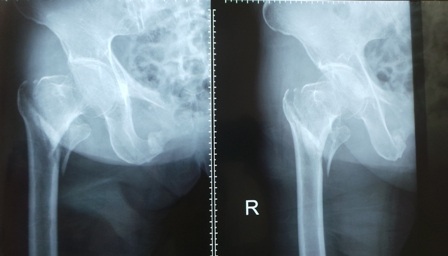

Qua chẩn đoán hình ảnh, bác sĩ phát hiện liên mấu chuyển cổ xương đùi phải của bệnh nhân gãy thành 4 mảnh lớn và nhiều mảnh nhỏ. Ngoài chấn thương trên, cụ bà còn bị suy thận mạn giai đoạn cuối, đái tháo đường, tăng huyết áp, bệnh tim thiếu máu cục bộ. Trước tình trạng cơ địa suy kiệt của người bệnh, ban đầu bác sĩ dự tính sẽ điều trị bảo tồn. Tuy nhiên, đây chỉ là phương án tạm thời nếu không được can thiệp triệt để, cụ bà sẽ phải nằm một chỗ chấp nhận cái chết đến từ từ vì nhiễm trùng, suy hô hấp.